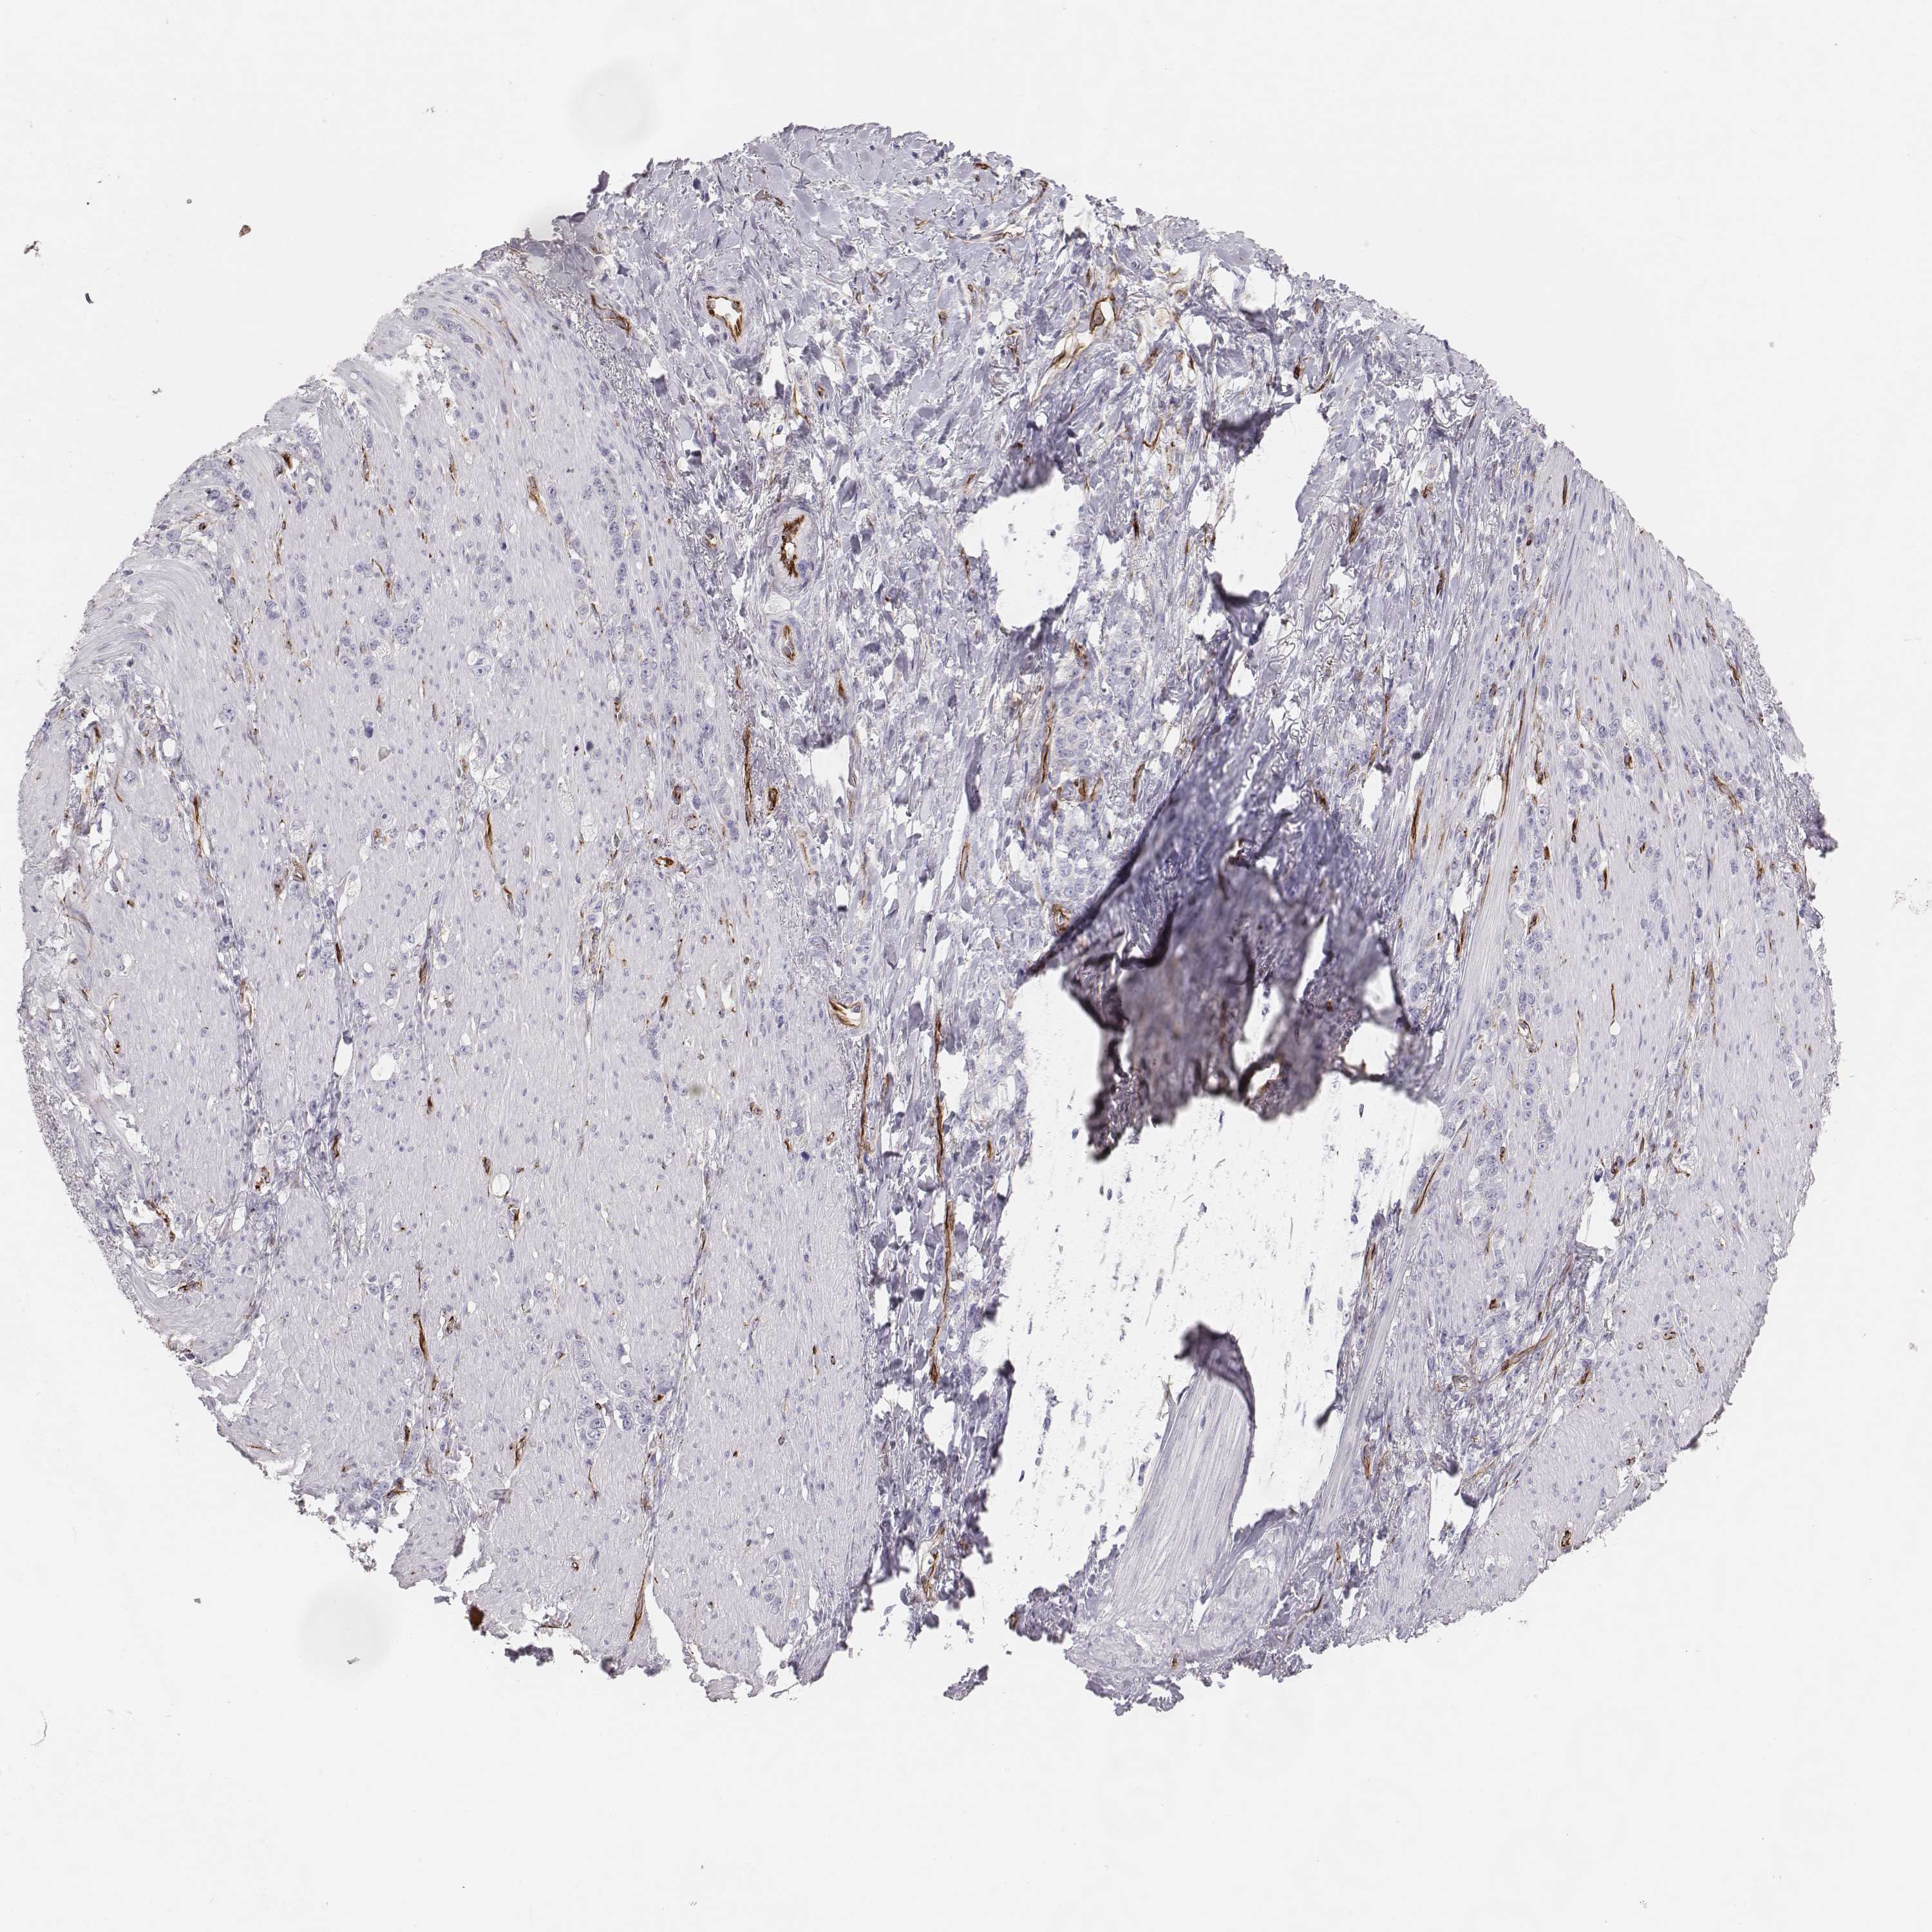

STOMACH CANCER - Protein expressioni

A mouse-over function shows sample information and annotation data. Click on an image to view it in a full screen mode. Samples can be filtered based on level of antibody staining by selecting one or several of the following categories: high, medium, low and not detected. The assay and annotation is described here.

Note that samples used for immunohistochemistry by the Human Protein Atlas do not correspond to samples in the TCGA dataset.

Antibody stainingi

Antibody staining in the annotated cell types in the current human tissue is reported as not detected, low, medium, or high, based on conventional immunohistochemistry profiling in selected tissues. This score is based on the combination of the staining intensity and fraction of stained cells.

Each image is clickable and will lead to virtual microscopy that enables deeper exploration of all samples and also displays staining intensity scores, fraction scores and subcellular localization as well as patient and tissue information for each sample.

Antibody HPA043261

Antibody HPA043264

Antibody HPA044028

Adenocarcinoma, NOS